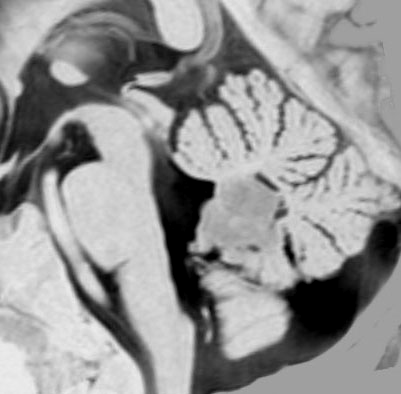

典型的な小脳虫部(小脳の真ん中)の髄芽腫です。横の方,ルシュカ孔へ伸びていないので上衣腫と区別できます。ガドリニウムという造影剤で白く写っています。